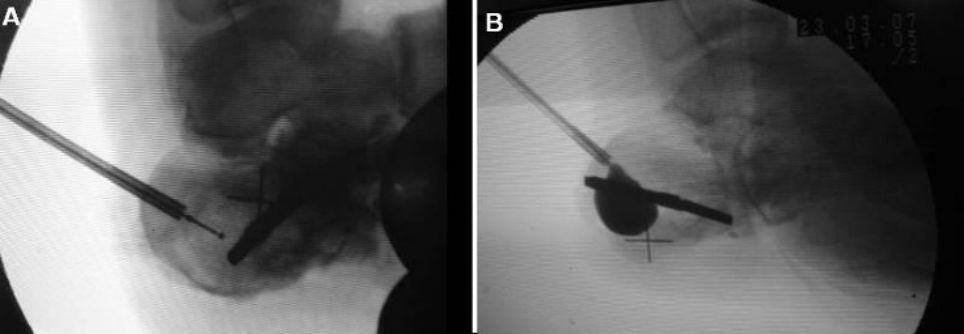

Placement of cannula and guide wire under fluoroscopy

Images before and after airbag inflation